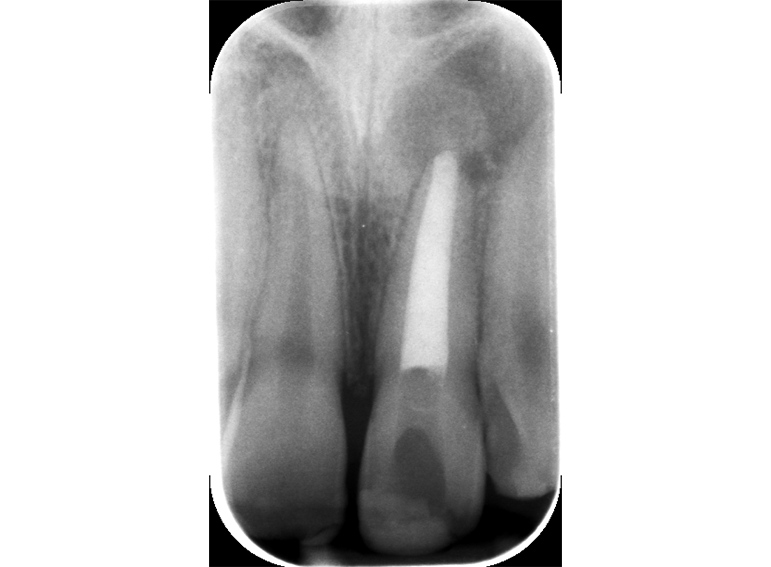

Root canal treatment including apexification of an immature incisor following dental trauma.